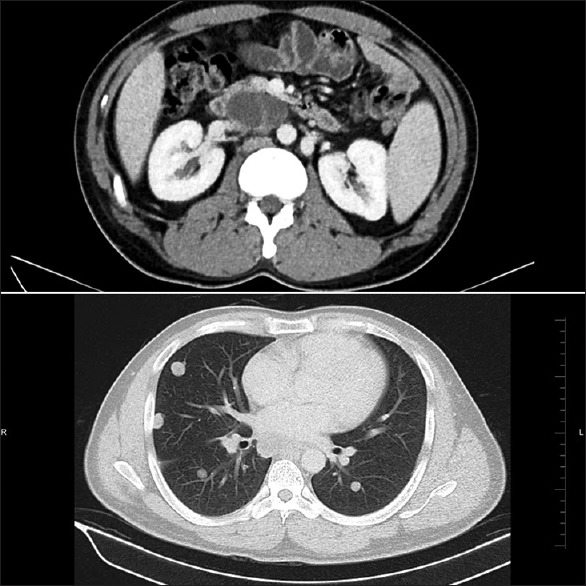

A 29-year-old male patient, with no prior known medical or dermatological comorbidities or any drug allergy, was diagnosed as a case of Stage IIIB testicular cancer. Contrast-enhanced computed tomography chest, and abdomen was suggestive of the lobulated lesion in paraaortic region with multiple bilateral lung nodules, mediastinal, and hilar lymphadenopathy [Figure 1]. Preoperative tumor marker analysis revealed serum alpha-feto protein level 12,100 ng/ml, serum beta human chorionic gonadotropin (HCG) level 2.39 mIU/ml, and serum lactate dehydrogenase (LDH) level 819 U/L. He underwent right high inguinal orchiectomy in May 2015. Final histopathology report was suggestive of mature cyctic teratoma of right testis with associated features of intratubular germ cell neoplasia [Figure 2]. Postoperative tumor marker analysis revealed serum alpha-feto protein level 126 ng/ml, serum beta-HCG level 2.39 mIU/ml and serum LDH level 292 U/L. Patients pulmonary and renal function tests were normal. He was started on bleomycin (30 units on days 1, 8, and15), etoposide (100 mg/m2 on day 1–5), and cisplatin (20 mg/m2 on day 1–5) based chemotherapy (BEP chemotherapy) as per our institutional protocol. However, after 3 cycles of chemotherapy, the patient started complaining of pruritic linear rashes which patient noticed first over the trunk and then gradually increased to involved skin over the chest, back, shoulder, and bilateral upper and lower limbs [Figure 3]. On physical examination, linear and streaked pigmentation were seen on bilateral upper limbs, lower limbs, and over chest and back. No other skin lesions were noted. There was no mucosal involvement or systemic upset. A clinical diagnosis of bleomycin-induced flagellate rash and postinflammatory pigmentation was considered. Routine laboratory investigations, including liver and renal function tests, were normal. Bleomycin was withheld from subsequent chemotherapy cycles, and the patient was prescribed betamethasone dipropionate ointment for local application twice a day for 2 weeks. On subsequent follow ups, the itching sensation was reduced was mild hyperpigmentation remained [Figure 4].

| Figure 2:Contrast-enhanced computed tomography abdomen chest showing multiple bilateral lung nodules with mediastinal and hilar lymphadenopathy

| Figure 2:Contrast-enhanced computed tomography abdomen chest showing multiple bilateral lung nodules with mediastinal and hilar lymphadenopathy